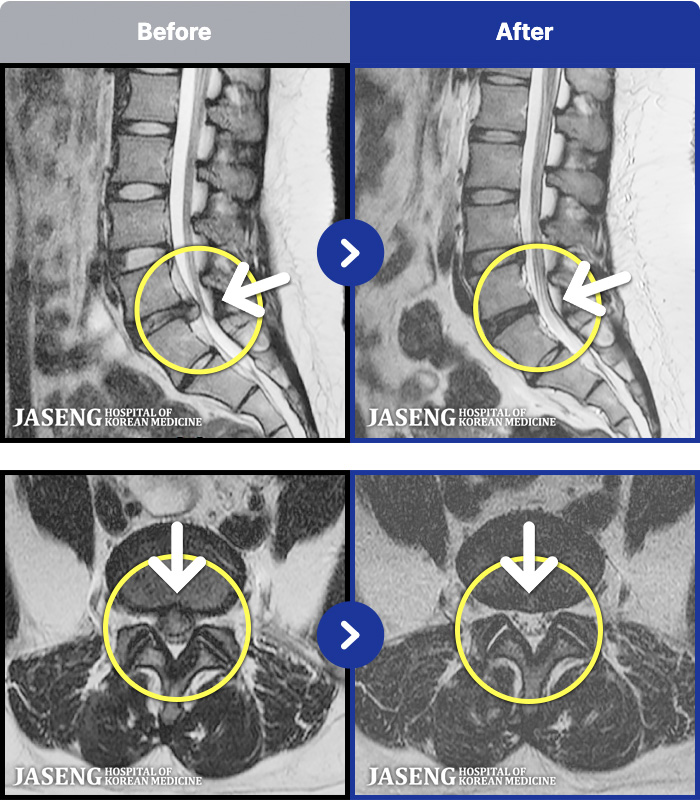

1,257 MRI ũ ʸ Ȯϼ.